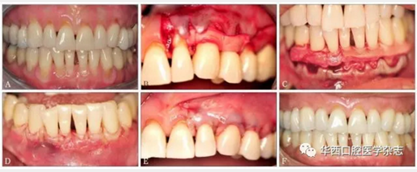

盡管使用ADM進(jìn)行膜齦手術(shù)的長(zhǎng)期療效一直存在爭(zhēng)議,但目前該技術(shù)仍是除游離結(jié)締組織外的另一個(gè)療效較為可靠的根面覆蓋手術(shù)(圖1)。

A:患者有廣泛性牙齦進(jìn)行性退縮,牙根暴露、敏感,臨床附著水平喪失,附著齦喪失;B、C:手術(shù)采用半厚瓣,翻過(guò)膜齦聯(lián)合線,常規(guī)根面處理,采用5-0可吸收線用連續(xù)褥式縫合方式將ADM縫合在唇頰側(cè);D、E:無(wú)張力情況下,采用5-0可吸收線行連續(xù)褥式縫合,半厚瓣冠向復(fù)位將ADM完全覆蓋;F:術(shù)后20個(gè)月,由于大量牙槽骨吸收,牙根表面沒(méi)有達(dá)到完全覆蓋,但是角化組織(附著齦)增加了3~4 mm。

圖 1 ADM結(jié)合冠向復(fù)位瓣手術(shù)